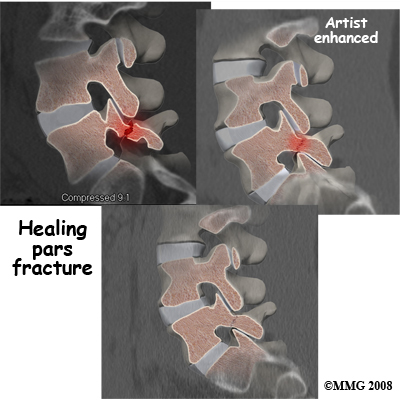

Two sets of bones form the spinal canal's . Two pedicle bones attach to the back of each vertebral body. Two lamina bones complete the ring. The place where the lamina and pedicle bones meet is called the pars interarticularis, or pars for short. There are two such meeting points on the back of each vertebra, one on the left and one on the right. The pars is thought to be the weakest part of the bony ring.

A condition called spondylolysis can lead to the slippage that happens with spondylolisthesis. Spondylolysis is a defect in the bony ring of the spinal column. It affects the pars interarticularis, mentioned earlier. This defect is most commonly thought to be a stress fracture that happens from repeated strains on the bony ring. Participants in gymnastics and football commonly suffer these strains. Spondylolysis can lead to the spine slippage when a fracture occurs on both sides of the bony ring. This slippage is called spondylolisthesis. The slippage is from I through IV, one being mild, IV often causing neurological symptoms. The back section of the bony ring separates from the main vertebral body, so the injured vertebra is no longer connected by bone to the one below it. In this situation, the facet joints can't provide their normal support. The vertebra on top is then free to slip forward over the one below.

If your doctor diagnoses an acute pars fracture that has the potential to heal, it may be recommended that you wear a rigid back brace for a few months. This usually occurs in children and teenagers who begin having back pain and see their doctor early on.

With cases of lumbar spondylolisthesis, doctors will usually order of the low back. The X-rays are taken with your spine in various positions. They can be used to see which vertebra is slipping and how far it has slipped.

If more information is needed, your doctor may order computed tomography (a CT scan). This is a detailed X-ray that lets the doctor see slices of the body's tissue. If you have nerve problems, the doctor may combine the CT scan with myelography. To do this, a special dye is injected into the space around the spinal canal, the subarachnoid space. During the CT scan, the dye highlights the spinal nerves. The dye can improve the accuracy of a standard CT scan for diagnosing the health of the nerves.

If your doctor diagnoses an acute pars fracture that has the potential to heal, it may be recommended that you wear a rigid back brace for two to three months. This usually occurs in children and teenagers who begin having back pain and see their doctor early on. X-rays may show a fresh fracture of the pars area of the vertebra on one, or both, sides. A CT scan or bone scan may be recommended to determine if the fracture is likely to heal. If so, a brace is recommended. X-rays or a CT scan may be ordered in six to eight weeks to see if the fracture is healing. IF not, the brace will be discontinued.